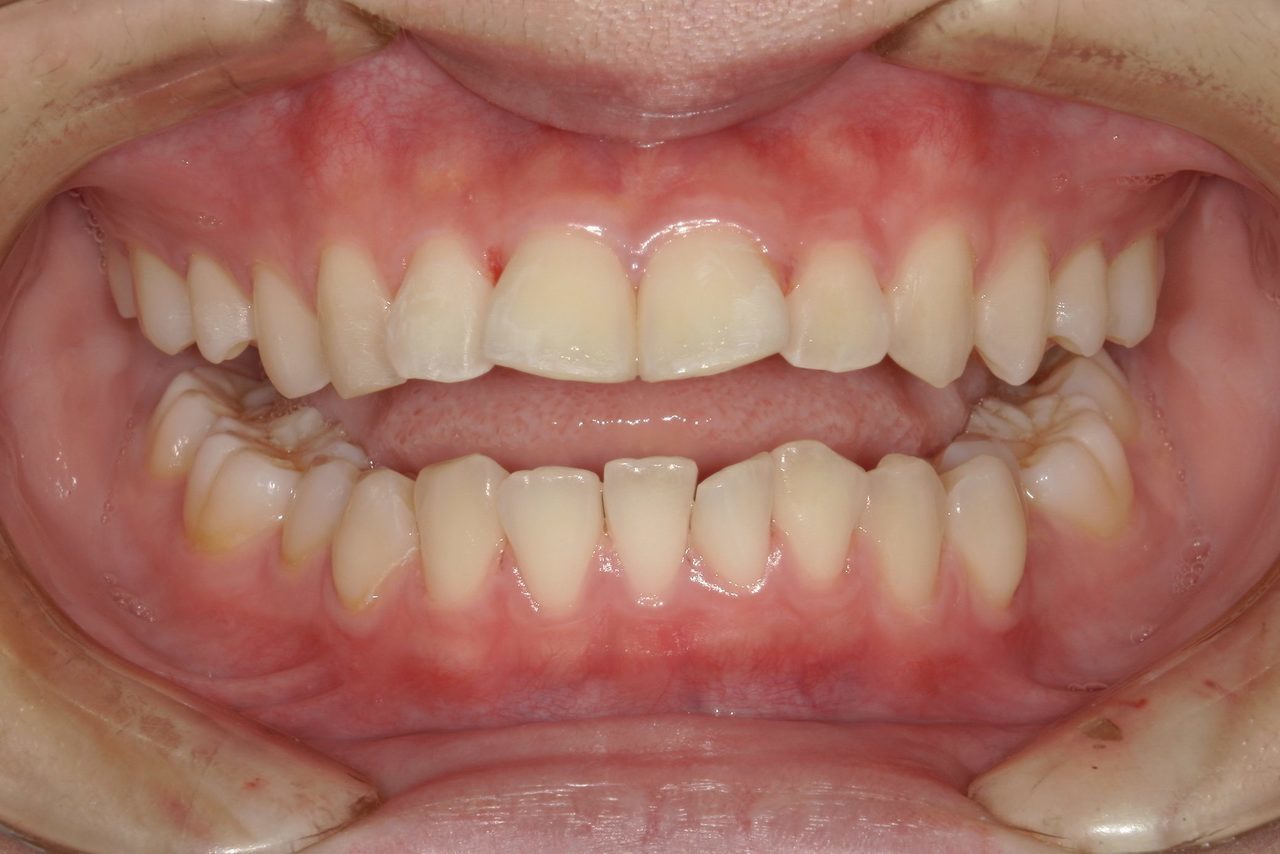

Before

浜松市中央区・自動車学校前駅のインビザラインの症例

Y.S. 30代男性

全体的にガタガタしているのが気になるという主訴だったため、上下左右第一小臼歯を抜歯し、叢生を並べました。

治療の期間:R3. 9/1〜R5. 10/31

治療の価格:88万円